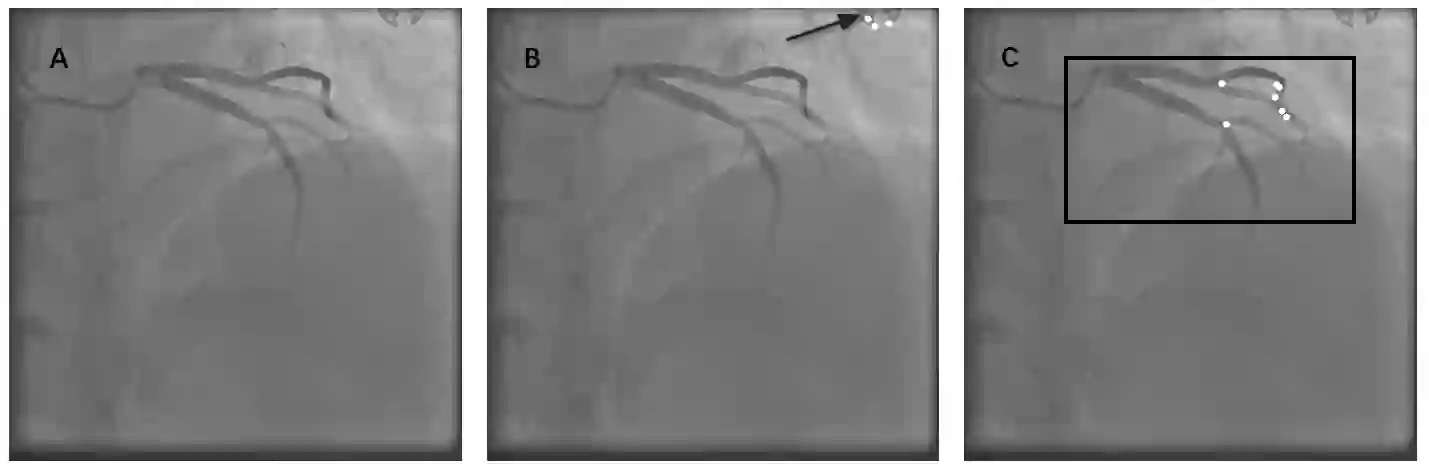

Automatic identification of proper image frames at the end-diastolic (ED) and end-systolic (ES) frames during the review of invasive coronary angiograms (ICA) is important to assess blood flow during a cardiac cycle, reconstruct the 3D arterial anatomy from bi-planar views, and generate the complementary fusion map with myocardial images. The current identification method primarily relies on visual interpretation, making it not only time-consuming but also less reproducible. In this paper, we propose a new method to automatically identify angiographic image frames associated with the ED and ES cardiac phases by using the trajectories of key vessel points (i.e. landmarks). More specifically, a detection algorithm is first used to detect the key points of coronary arteries, and then an optical flow method is employed to track the trajectories of the selected key points. The ED and ES frames are identified based on all these trajectories. Our method was tested with 62 ICA videos from two separate medical centers (22 and 9 patients in sites 1 and 2, respectively). Comparing consensus interpretations by two human expert readers, excellent agreement was achieved by the proposed algorithm: the agreement rates within a one-frame range were 92.99% and 92.73% for the automatic identification of the ED and ES image frames, respectively. In conclusion, the proposed automated method showed great potential for being an integral part of automated ICA image analysis.